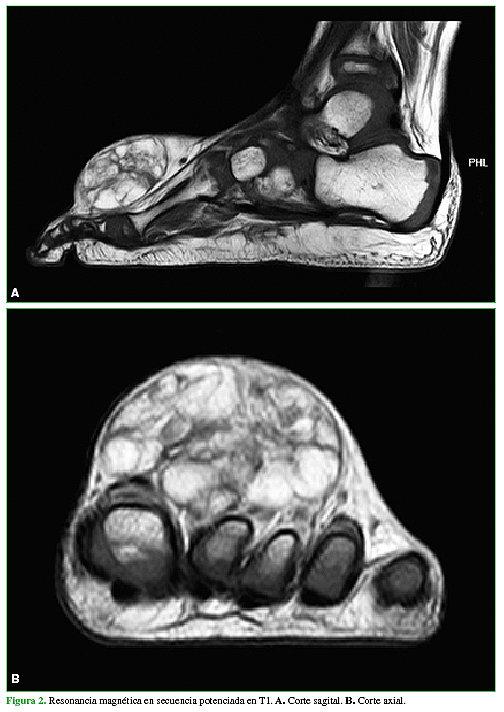

Lipoblastoma: una causa inusual de tumoración del pie en niños